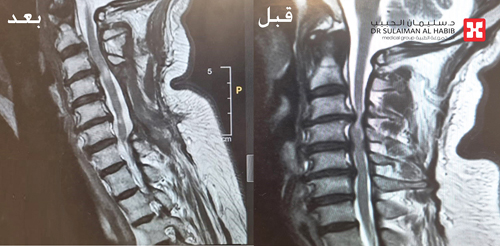

وقد كشفت النتائج بدقة عن وجود ضغط شديد ومتزايد على الحبل الشوكي بالفقرات العنقية في الرقبة، وبناء على المعطيات والنتائج قرر الفريق الطبي المعالج التدخل الجراحي العاجل، وذلك لإنقاذ الحبل الشوكي من الاعتلال والحد من إصابته بمزيد من المضاعفات، حيث تم تحضير المريض وتجهيز غرفة العمليات بطاولة متخصصة لمثل هذه الحالات تُعرف باسم «Jackson Table»، والتي توفر للفريق الطبي القدرة على دوران المريض في أي اتجاه وقت العملية، وكذلك توفير جهاز « Mayfield» الذي يساعد في دقة النتائج وتثبيت الرأس أثناء الجراحة.

وأوضح د. السبيعي أن العملية الجراحية استغرقت 5 ساعات متواصلة تحت التخدير العام، وتم فيها عمل فتح جراحي والوصول لمنطقة الفقرات العنقية، ومن ثم إزالة الضغط الشديد على الحبل الشوكي باستخدام المايكروسكوب الجراحي، ونقل بعدها المريض لجناح التنويم، حيث تلقى رعاية طبية فائقة على مدار يومين، وقد استطاع الوقوف والمشي بشكل تام وانتهت لديه نوبات الألم وتنميل الأطراف، وخرج بعدها من المستشفى وهو بصحة ممتازة ولله الحمد.